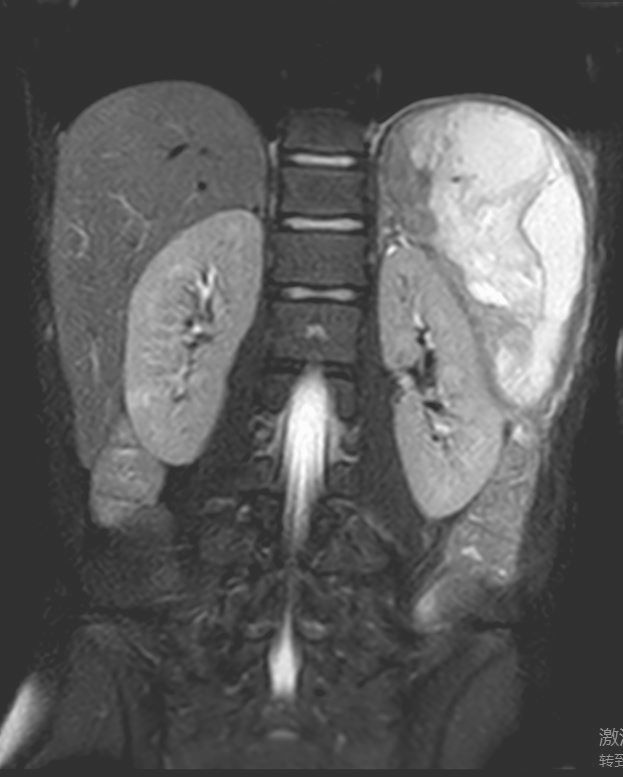

普外科接诊后,副主任医师胡明结合外院CT与本院MRI检查结果,明确诊断为“脾坏死液化伴积气积脓” (范围约152.6mm*102.5mm*58mm)。